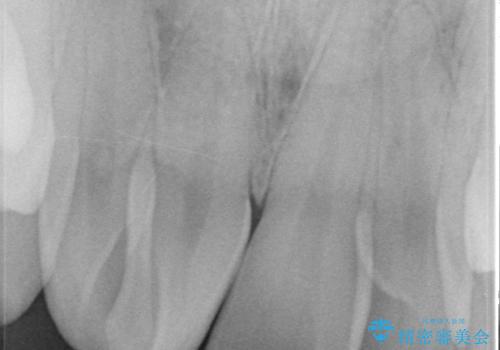

左右の1番目の歯は傾きが大きいため、セラミッククラウンにするにあたり神経治療を行うことを御了承頂いた上で、前歯4本をオールセラミッククラウン(スペシャル)により補綴しました。

- 根管治療により類似の全ての症例の問題が解決するわけではなく、症例はあくまでも一例です

- 根管治療により痛みや腫れがひかない事や、術後に痛みや腫れが生じる事、治療によるファイル破折やパーフォレーションなどの偶発症、術後の歯根破折を生じる可能性もあります